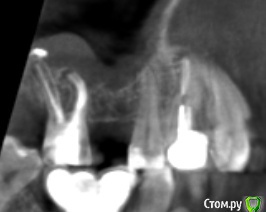

Fin Опубликовано 20 марта, 2020 Поделиться Опубликовано 20 марта, 2020 Здравствуйте коллеги.Планируется имплантация в области 1.6. Но зуб 1.7 с небольшой кистой в гайморовой пазухе, перелечить невозможно СО пазухи в этой области отечна.. Пациенту требуется синус лифтинг. Думаю что нужно удалять 1.7 и после делать имплантацию с ЗСЛ или ОСЛ. На данный момент пациент немного противится, поэтому и решил спросить. Как бы вы поступили, поставили бы короткий имплантат, или ЗСЛ без удаления 7ки. Буду благодарен Вашим ответам. Ссылка на комментарий

Irouil Опубликовано 20 марта, 2020 Поделиться Опубликовано 20 марта, 2020 Удалил бы, конечно Тут транскрестально поднять не проблема, не надо короткий, можно даже 10, пожалуй, но зуб этот надо удалять по любым показаниям. Пациент если этого не понимает, то я бы просто отказал 1 Ссылка на комментарий

Irouil Опубликовано 20 марта, 2020 Поделиться Опубликовано 20 марта, 2020 Я бы посмотрел кт в области зуба) может и одномоментно Если отсроченно, то 2 месяца. Но если терапевт не готов на эндодонтию - то удалил бы в любом случае А если терапевт берётся лечить - то я бы подождал две недели после пломбировки и посмотрел симптоматику, дальше закрытым. Если брать винт пошире, то апертура будет почти как латеральная, дно ровное, если пробку костную продавите - поднять несложно. 1 Ссылка на комментарий